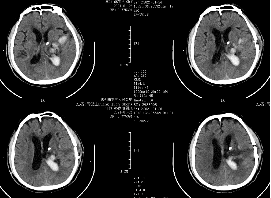

術(shù)前ct(白色為血腫)